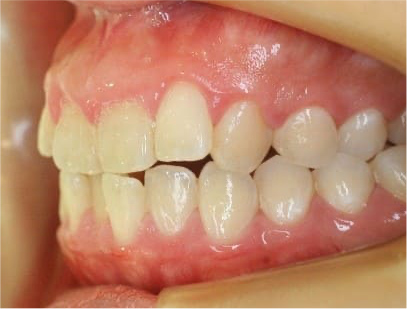

前歯にデコボコがあり、前歯が咬み合っていない症例

上下の前歯が咬んでいない事、上の前歯にデコボコがある事を主訴として来院されました。

通常通りの検査を行い「前歯部にデコボコを伴う開咬」と診断されました。

• 右側

• 左側